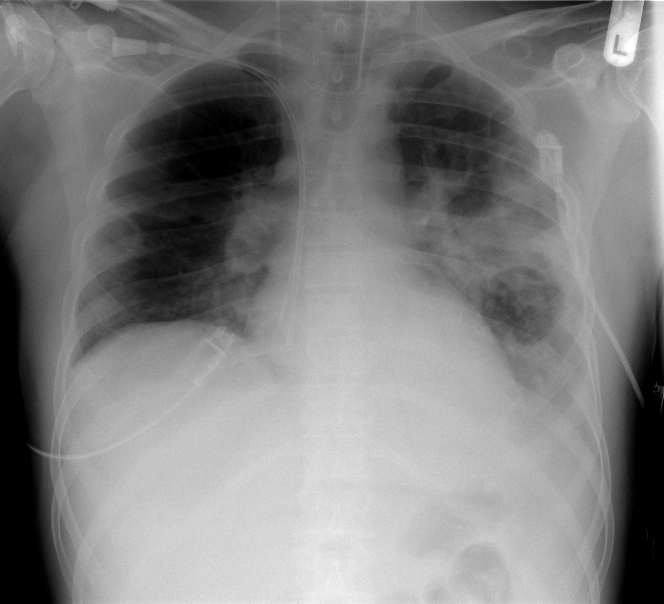

Диагностицирането на вирусни пневмонии изисква комбинация от клинична оценка, лабораторни тестове и образни изследвания.

- Образни изследвания: Рентгенография и компютърна томография (КТ) на гръдния кош.

- Диагностика: Лаваж и PCR тестове за откриване на гъбичното ДНК, както и рентгенови снимките на гърди и бял дроб.